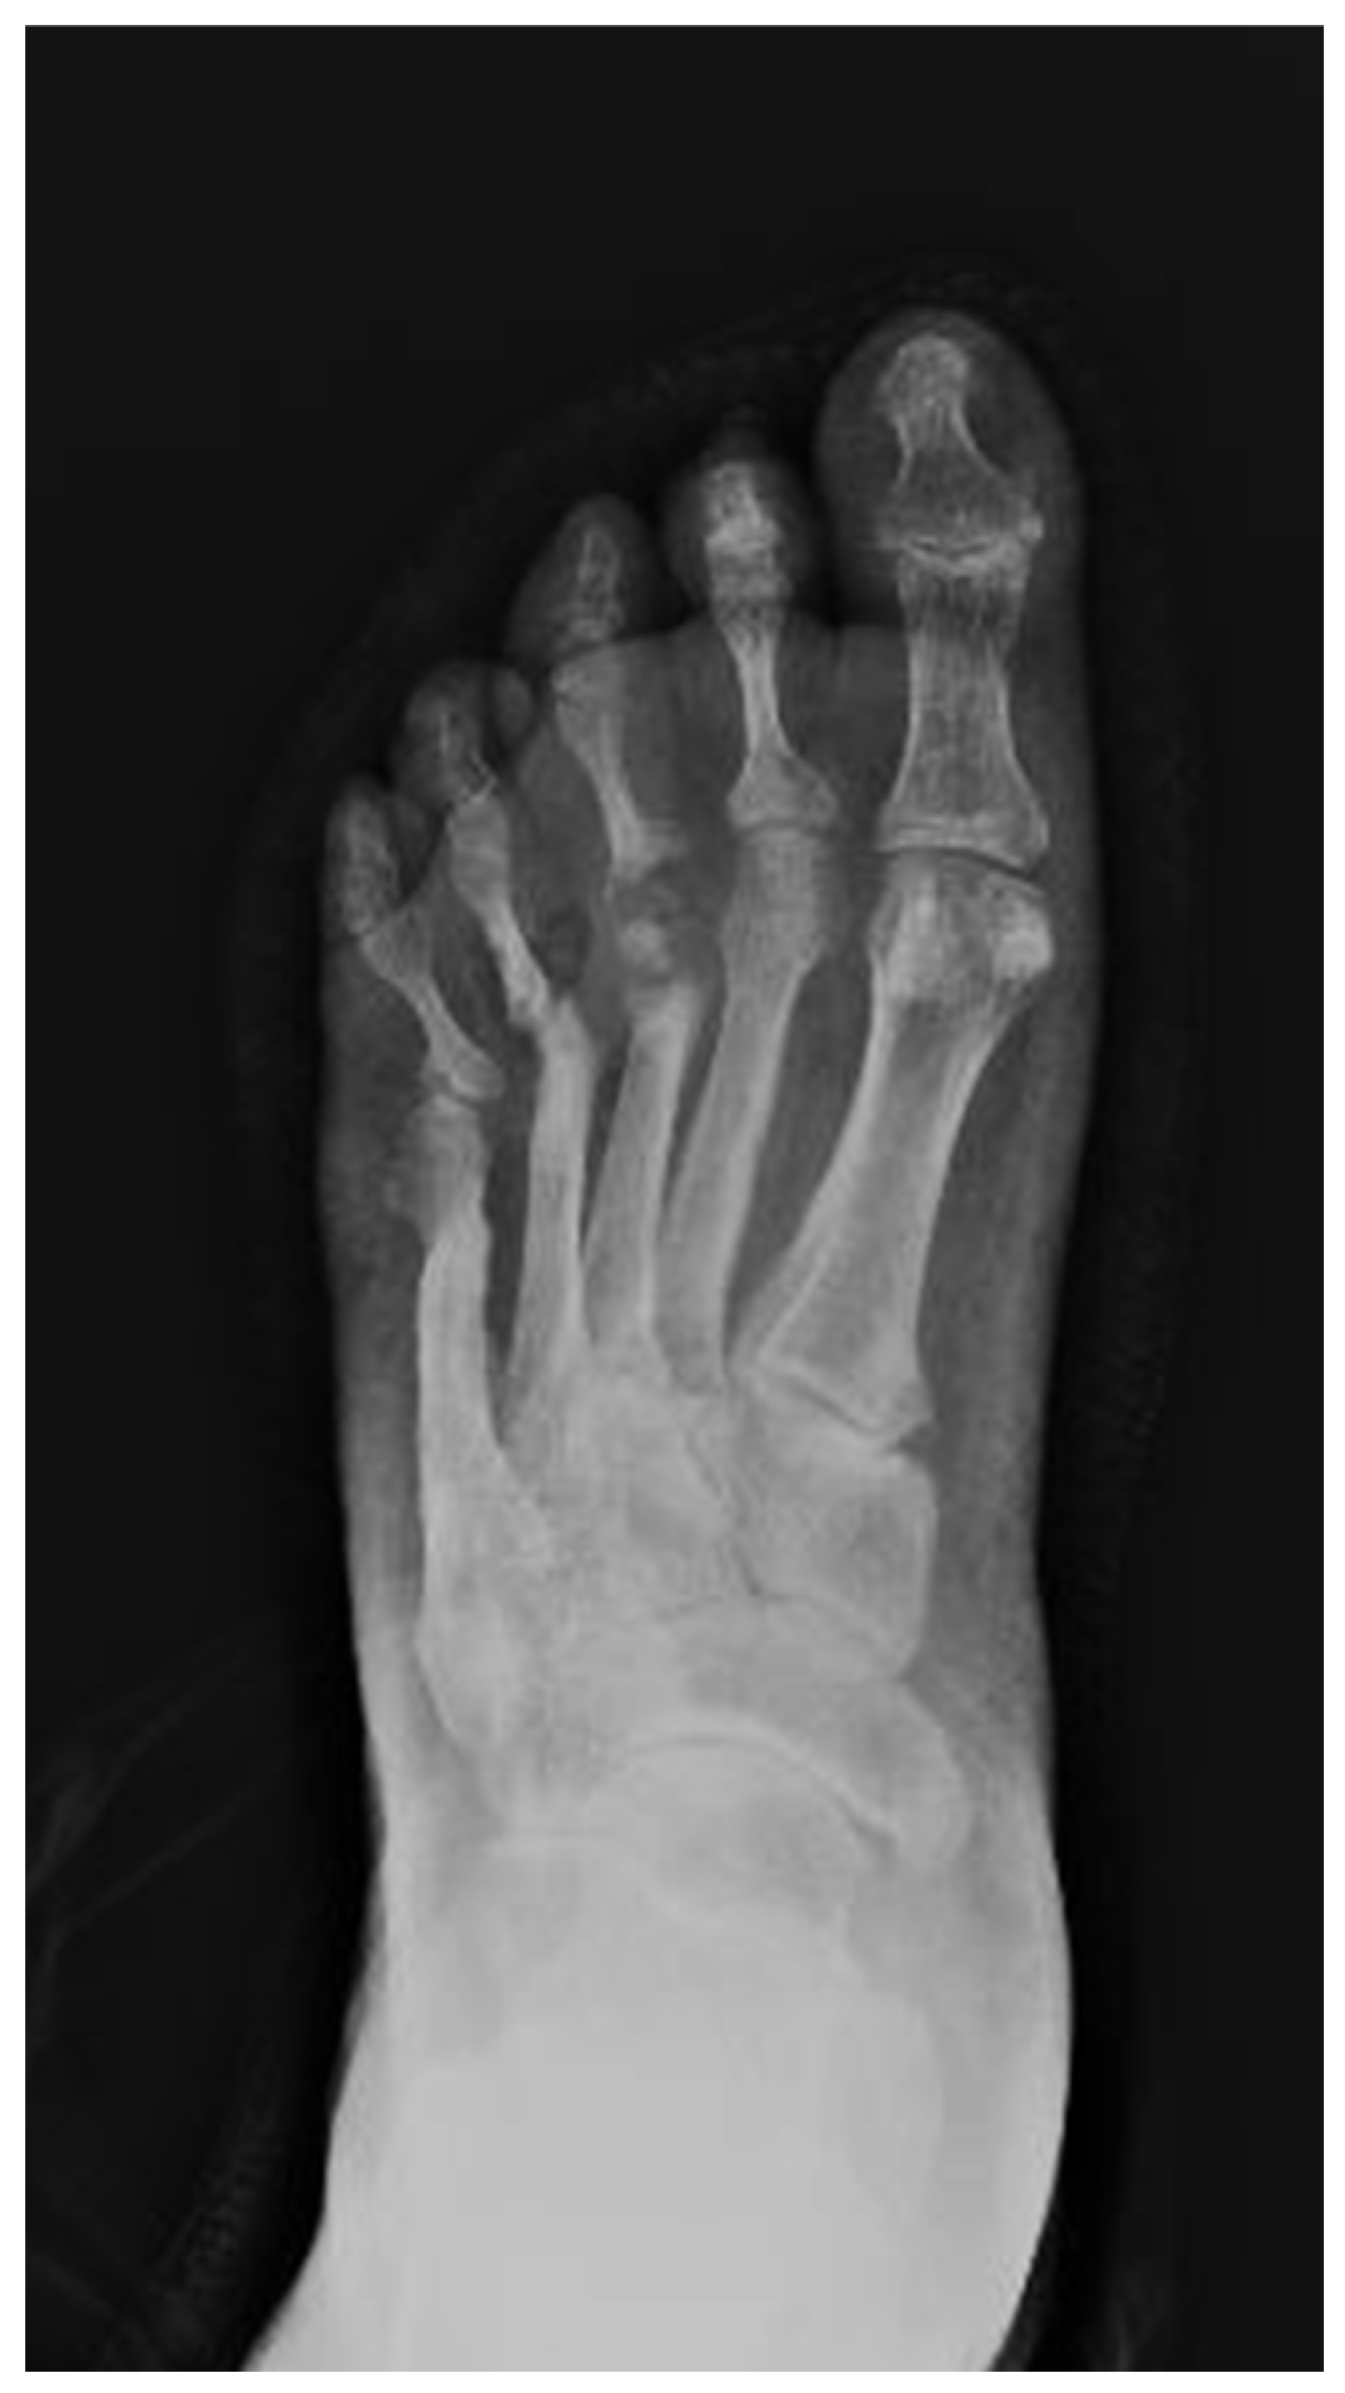

3. X-Rays